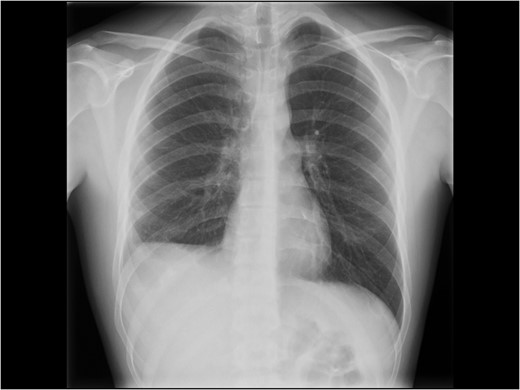

An adolescent male suffered a high-velocity fall while exercising ski-sports in the Alps. He suffered a severe blunt injury with temporary loss of consciousness and was brought to a local hospital where initial work-up and imaging showed no head injury other than a concussion, a right-sided pulmonary contusion with haematothorax and a grade II liver laceration involving segment 8. A right-sided chest drain was placed (Fig. 1) and was kept for several days with strict bed rest and monitoring under conservative management. After 14 days, he eventually was deemed fit for ground-ambulance transfer to our hospital. The chest drain was removed 4 days prior to departure.

Initial chest X-ray after placement of thoracic drain. White arrows note a high-stand of the right diaphragm, black arrow points to chest drain.

On admission after transfer to our hospital he had stable vital signs, with none or little complaints or symptoms. The transferred radiological images from the primary hospital were reviewed and gave immediately suspicion of additional pathology in the right hemithorax, based on a prominent right-sided high-stand of the diaphragm (Fig. 1). A CT scan was made showing a grade II liver laceration and a herniated liver through a large right-sided defect of the right diaphragm (Fig. 2A and B).